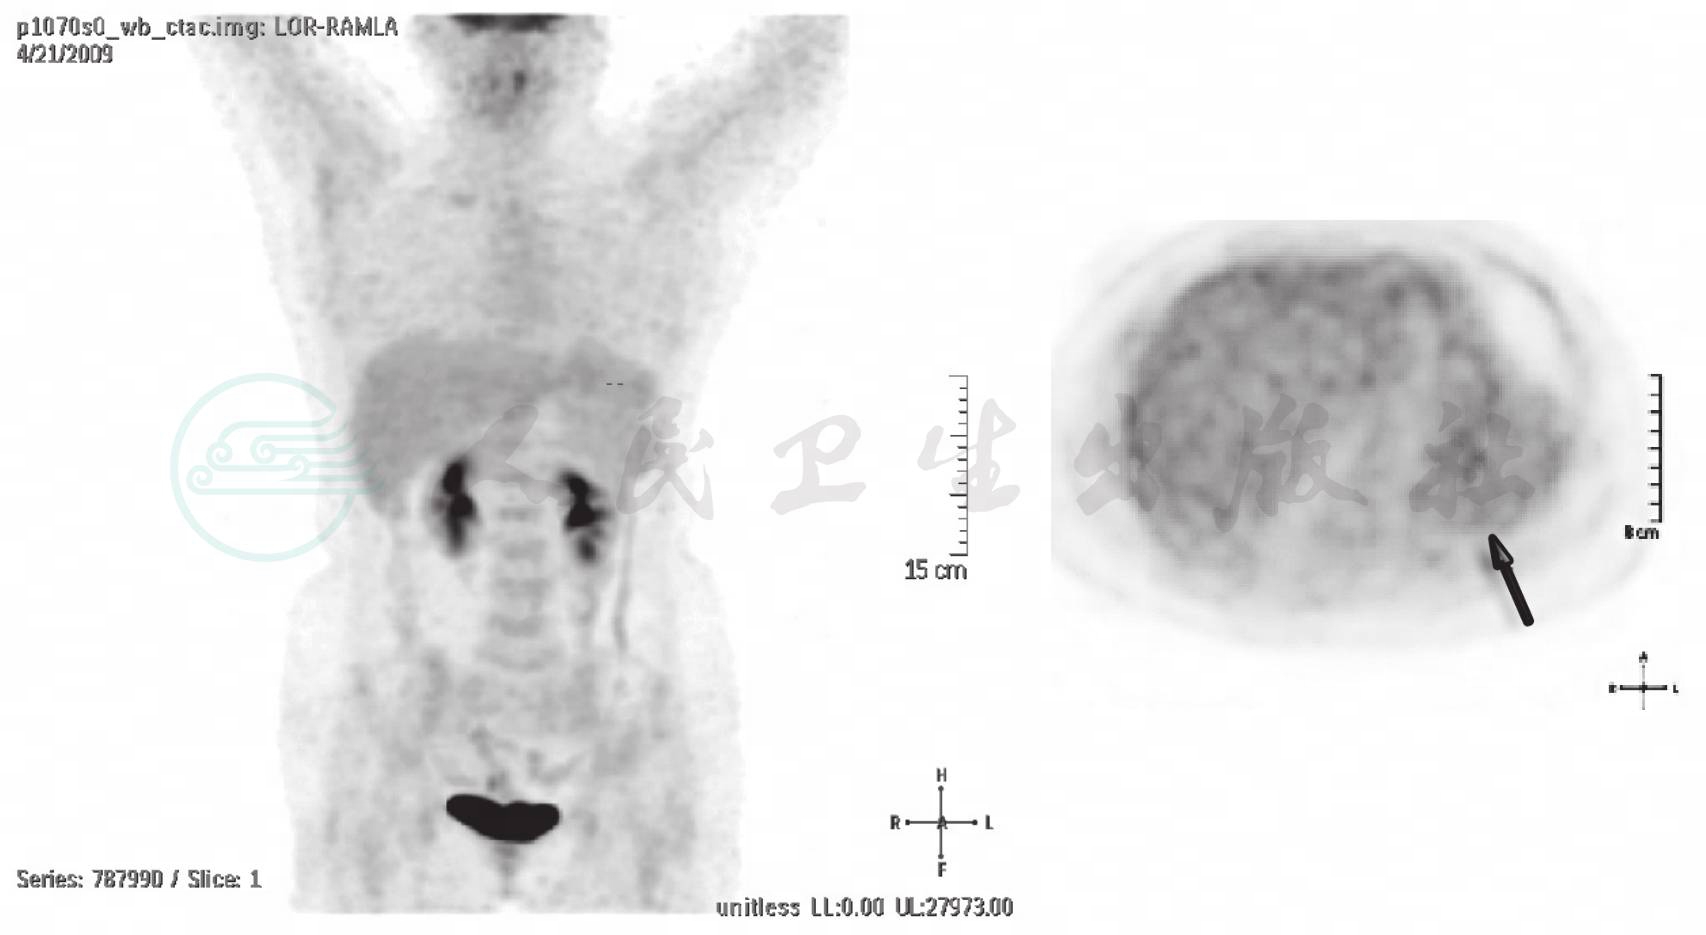

图2 PET三维透视图和横断面图像

左上腹软组织团块部位可见轻度高代谢(十字标或箭头)

左上腹可见不规则囊实性肿物,大小约(8cm×9cm×7cm),内密度不均匀,可见多个结节状软组织密度及片状液体影,与胃分界不清,与左侧膈肌关系密切。PET软组织结节部位可见片状轻度高代谢,SUVmax值2.7,2小时延迟显像SUVmax值2.6。